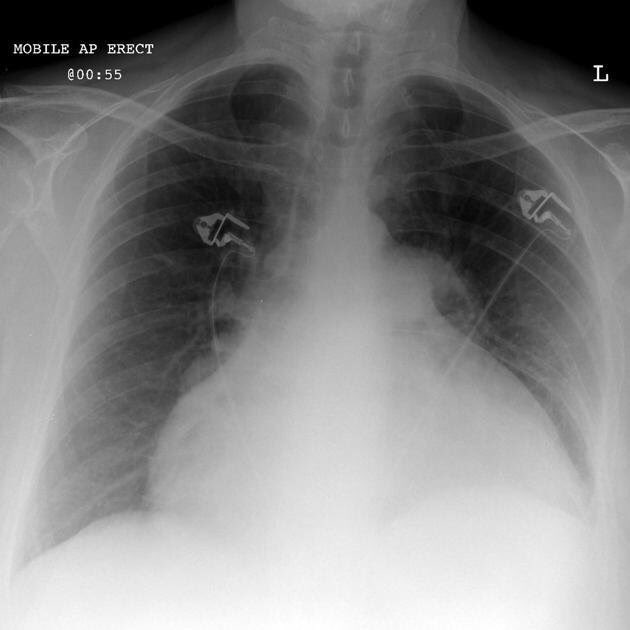

Signe de la "cantimplora": Vessament pericàrdic